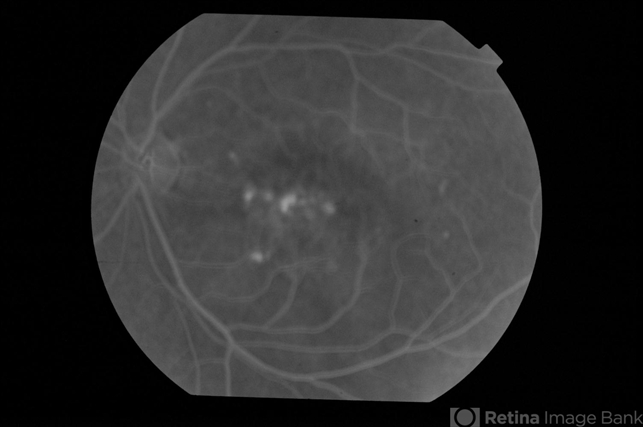

- CSCR subfoveal leak

- 52-year-old male with left eye CSCR of 6 months duration. Mid-phase fluorescein angiogram shows multiple leaks including a sub-foveal one. He was treated with PDT with complete resolution of fluid.